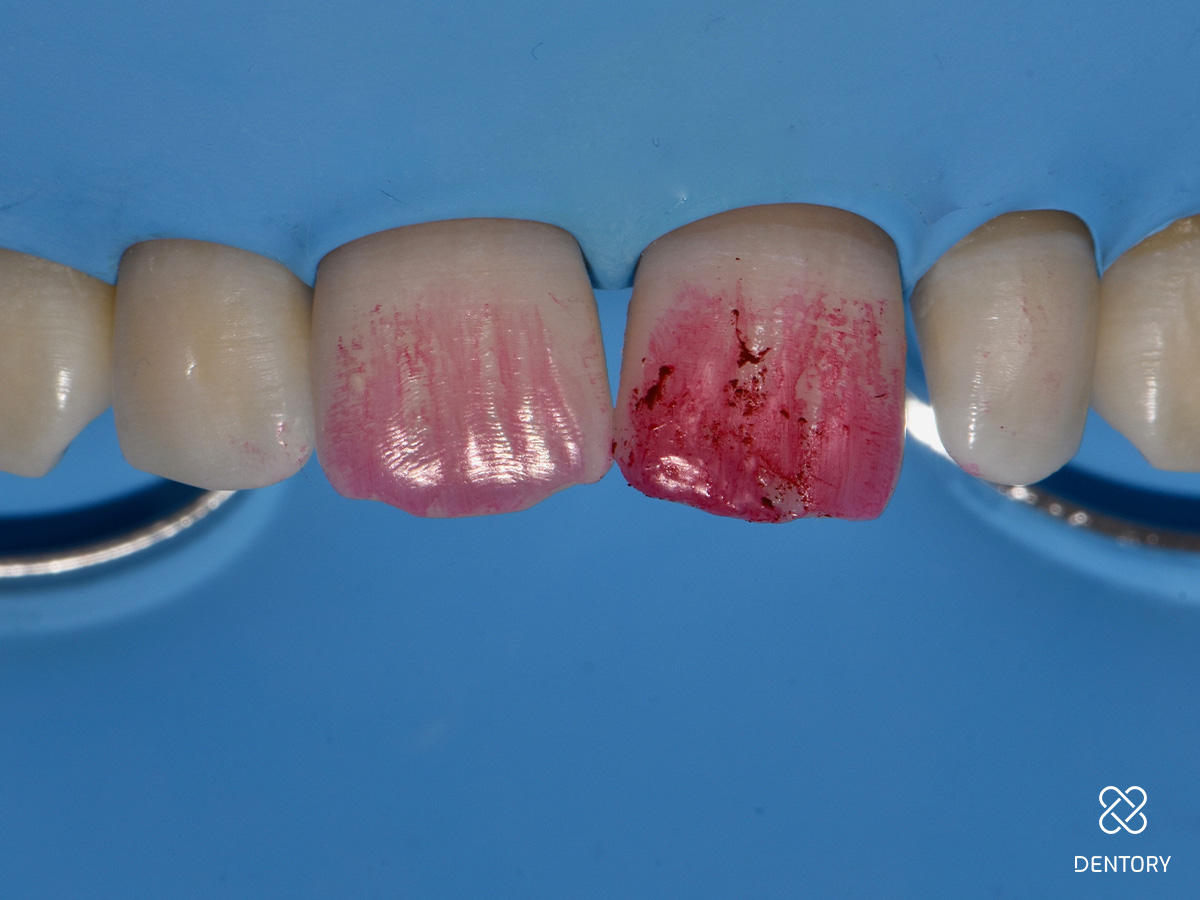

Abbildung 1

Farbbestimmung: Für die Farbauswahl werden Komposit-Proben direkt auf den Zahn platziert und ausgehärtet. In diesem Fall wurden A2 (o.r.) und Enamel Light (EL, u.r.) gewählt.